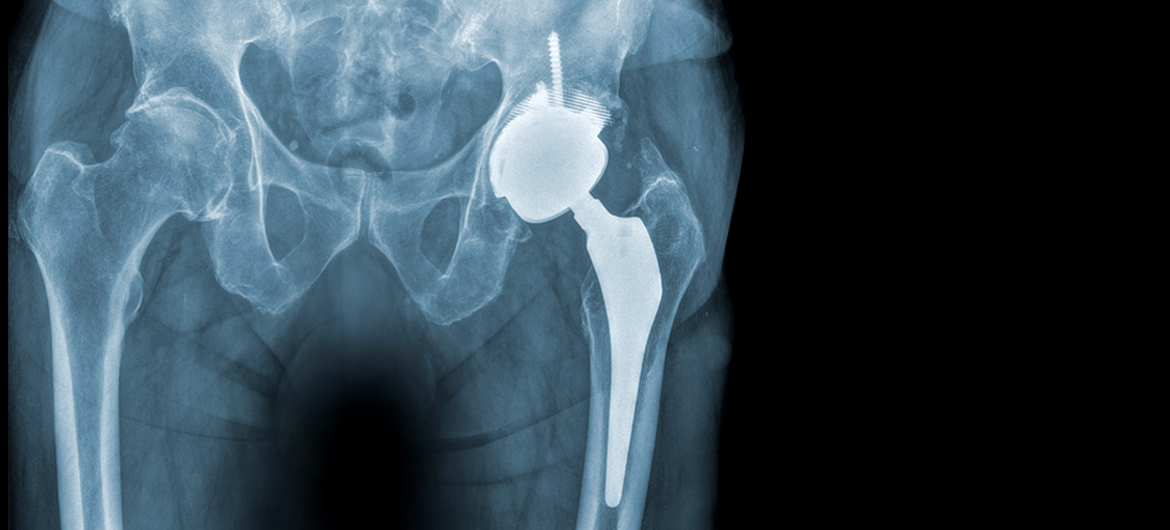

«Hüftschmerzen bei Arthrose: Wann ist ein künstliches Hüftgelenk sinnvoll?»

Anhaltende Hüftschmerzen schränken die Lebensqualität und Mobilität stark ein und werden häufig durch Arthrose verursacht. Doch nicht immer haben die Schmerzen ihren Ursprung im Hüftgelenk.

Bevor ein Gelenkersatz in Erwägung gezogen wird, ist eine sorgfältige fachärztliche Abklärung entscheidend, um mögliche andere Ursachen, wie Schleimbeutelentzündungen, Wirbelsäulenerkrankungen oder muskuläre Probleme, auszuschliessen. Wenn alle anderen Behandlungsoptionen ausgeschöpft sind, kann ein künstliches Hüftgelenk eine sinnvolle und wirksame Therapie darstellen.